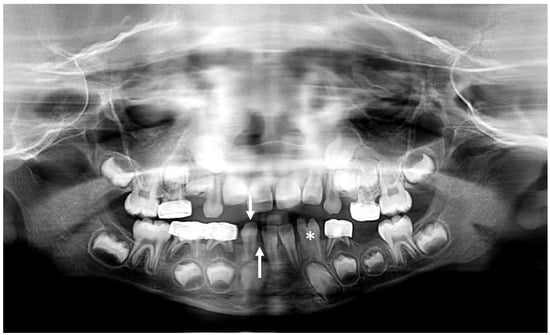

3.2. Dental Development

3.3. Radiologic Correlations of Embryological Development